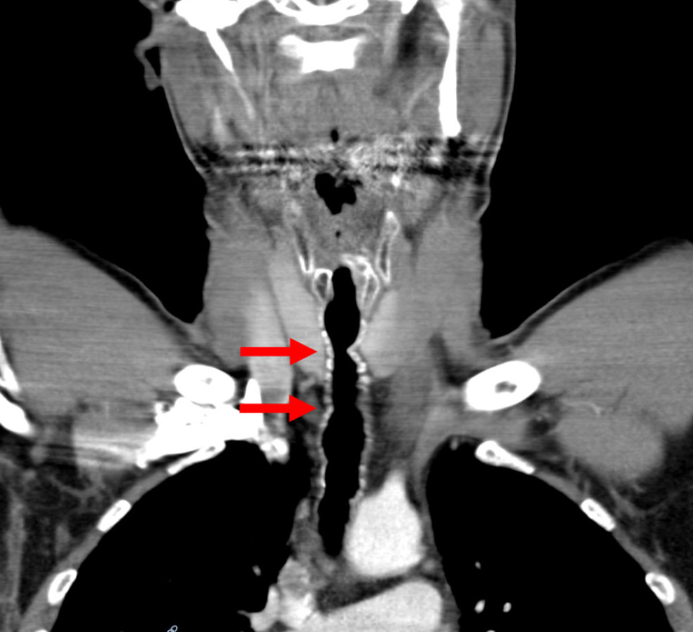

"Wir stellen einen Fall einer erfolgreichen endoskopischen Behandlung von intratrachealem Haarwuchs bei einem rauchenden Patienten vor", wie es im American Journal of Case Reports wörtlich heißt. Der betreffende Patient war mehr als dreißig Jahre lang Raucher, das erste in seinem Hals gewachsene Haar spuckte er 2006 aus. Seither wurde an ihm eine Reihe von Tests und Untersuchungen durchgeführt.

Haarwurzeln restlos verödet

Forscher fanden heraus, dass der Haarwuchs einst durch das Rauchverhalten des Oberösterreichers ausgelöst wurde. Die fünf bis zehn Zentimeter langen Haare im Hals wurden seit ihrer Entdeckung mehrmals entfernt, bis die Wurzeln vor kurzem endgültig verödet werden konnten. Dass seither keine Haar mehr nachwuchsen, dürfte auch dem konsequenten Rauchstopp des Patienten geschuldet sein.